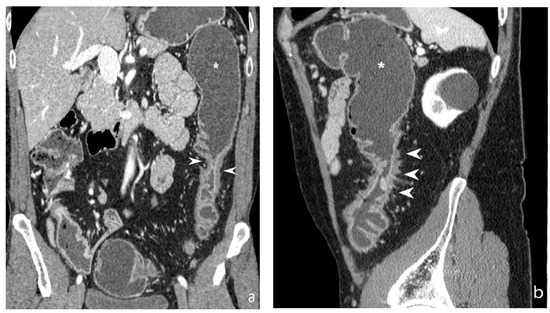

5.2. Fibro-Stenotic Subtype